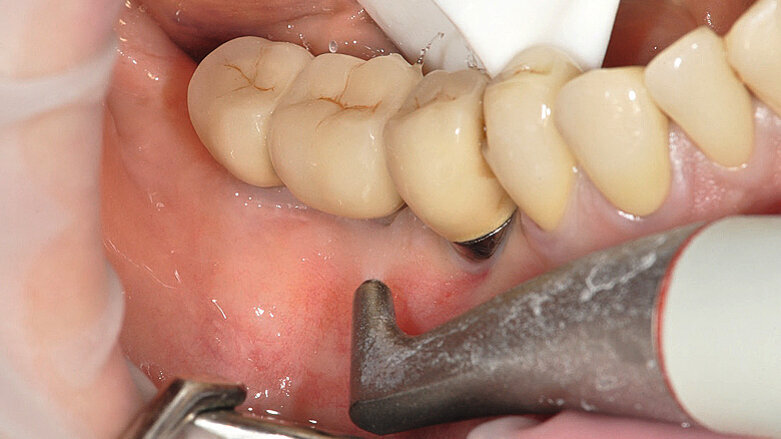

Figs. 1a : Implant en position 14 affecté par une péri-implantite : sondage péri-implantaire avec la couronne prothétique in situ

Fig b : Implant en position 14 affecté par une péri-implantite : sondage péri-implantaire après retrait de la couronne prothétique.